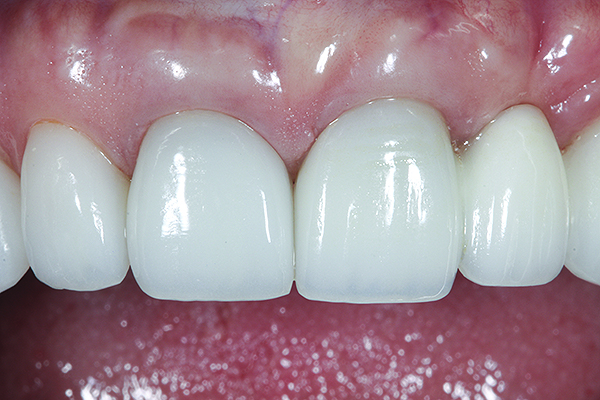

Fig 19 and Fig 20. Four-month follow-up appointment. The soft tissues had healed within normal limits (Fig 19), and the patient was pleased with the esthetic outcome of the definitive restoration (Fig 20).

Figure 19

Figure 20

The crown was inserted and secured with a luting composite (Multilink® Automix, Ivoclar Vivadent) (Figure 17); a radiograph confirmed complete removal of excess cement (Figure 18). At the 4-month follow-up appointment, the soft tissues were healed within normal limits, and the patient was pleased with the esthetic outcome of the definitive restoration (Figure 19 and Figure 20).